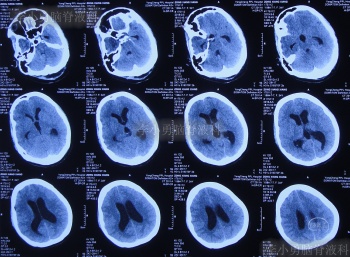

小脑扁桃体下疝减压术后20天即2019年3月6日,查头颅、颈椎核磁发现仍有脊髓空洞(图-8、图-9)。

图-8:2019年3月6日头颅核磁

图-9:2019年3月6日头颅核磁

小脑扁桃体下疝减压术后28天即2019年3月14日,仍头痛剧烈,间断发热,转至上级的河南省郑州市某三甲医院。于2019年3月15日,查头颅CT(图-10)后进行了腰大池引流治疗,引流后头痛仍无缓解,引流出脑脊液呈淡黄色,浑浊,考虑颅内感染。

图-10:2019年3月15日头颅CT